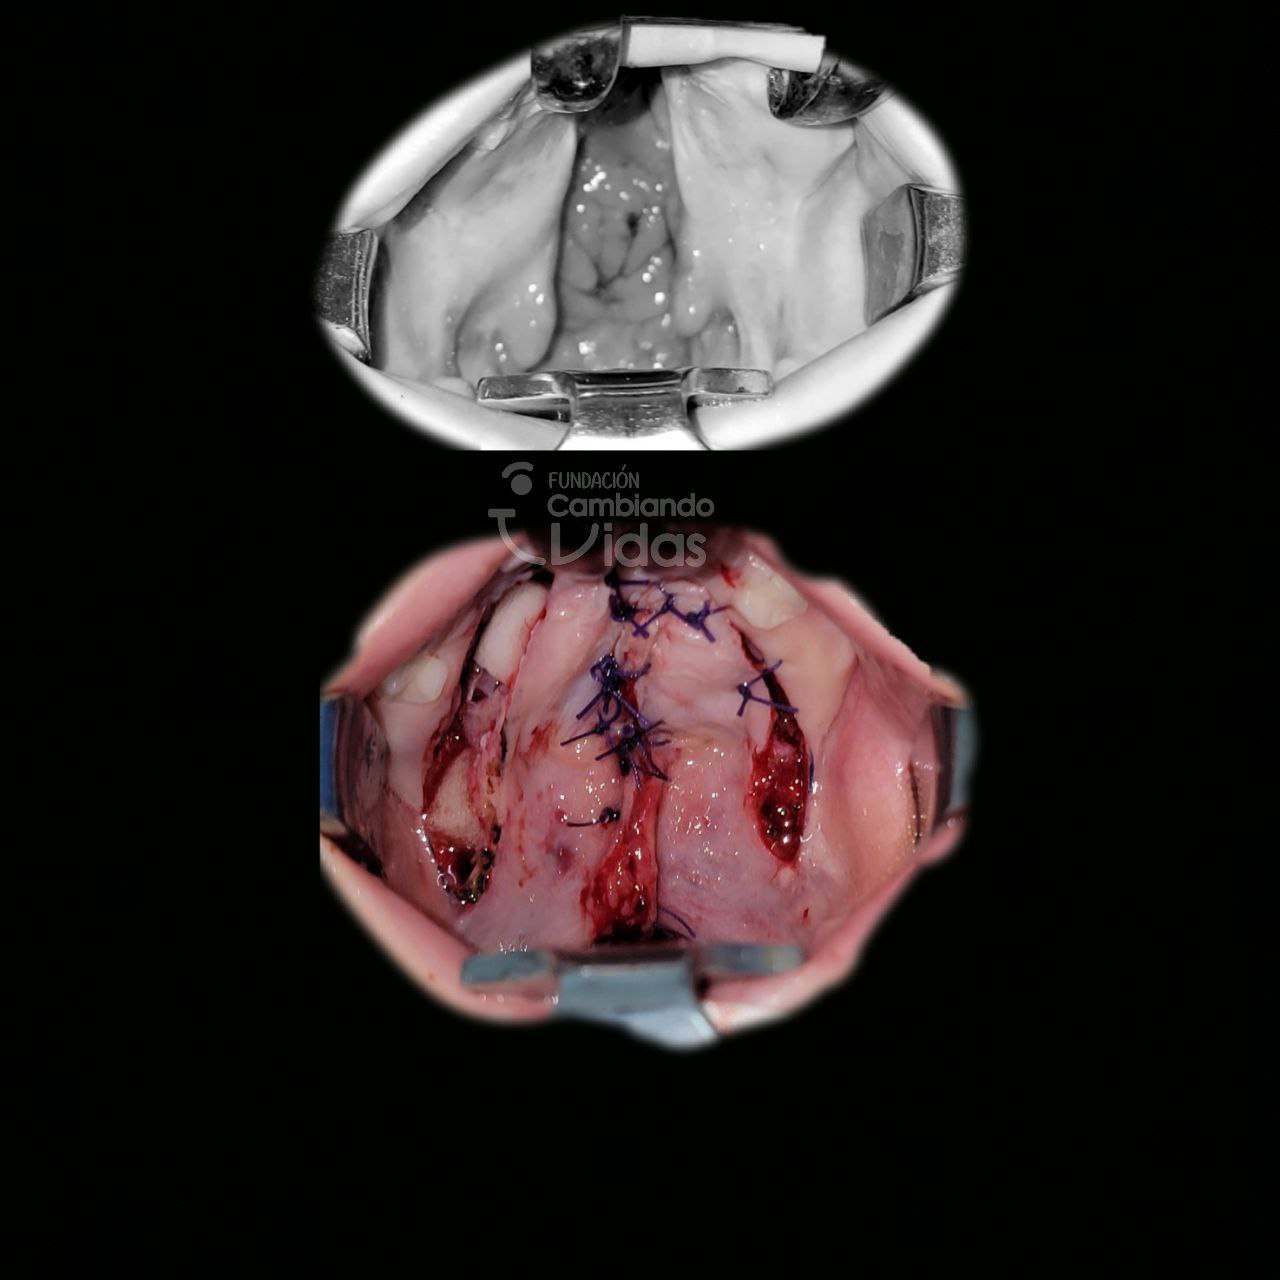

Amanda Rodriguez

Intervención Quirurgica: Palatoplastia Primaria Tipo II